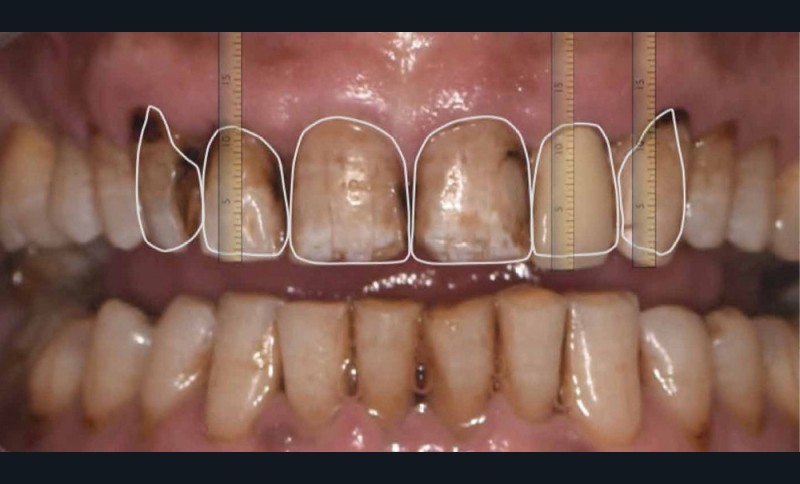

La première étape prothétique consiste en la réalisation de photographies intra/exo buccale et d’une empreinte numérique initiale. Cela permettra la réalisation d’une analyse esthétique (fig. 2) par la technique du Digital Smile Design (DSD) dans l’objectif :

- d’une meilleure communication avec le patient ;

- d’une meilleure communication avec le technicien de laboratoire. L’artisan céramiste doit avoir les références faciales pour travailler dans les meilleures conditions : lignes bi-pupillaires et bi-commissurales, axe médian, forme du visage pour intégrer la notion de « visagisme » ;

- de valider la position des bords incisifs et de la ligne des collets ;

- de réaliser une céraplastie prospective (wax-up) et un masque (mock-up) qui guideront nos préparations.

Dans notre cas, il faudra diminuer le bord libre de 12, 22 et 23. Les autres dents ne subiront aucun changement dimensionnel.